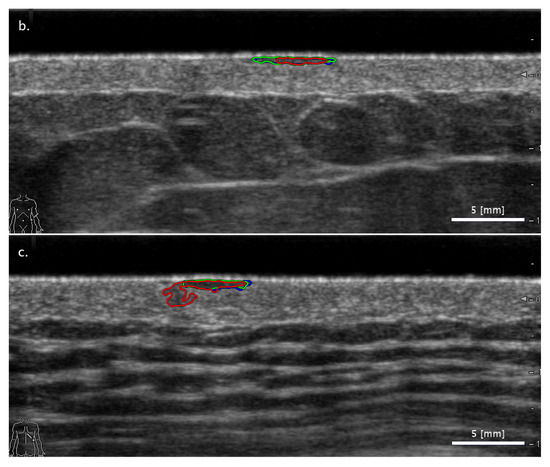

3.2. Comparison of FA and SA Classification Performance with Representative Images

3.2.1. Cases When FA Fails While SA Methods Perform Correctly

3.2.2. Cases When the Two SA Methods Return Different Classifications

3.2.3. Cases When the SA Methods Both Fail While the FA Method Performs Correctly

3.3. Sensitivity of Classification to Changes in Lesion Segmentation